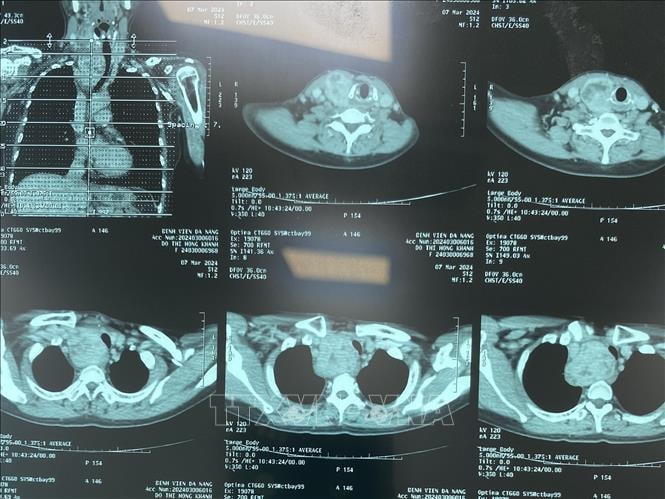

Trước đây, việc in phim đối với các dịch vụ chẩn đoán hình ảnh như chụp X-quang, chụp cắt lớp vi tính (CT) và chụp cộng hưởng từ (MRI),… nhằm cung cấp kết quả chẩn đoán dưới dạng vật lý, phục vụ công tác khám bệnh, điều trị, hội chẩn, chuyển tuyến, lưu trữ hồ sơ bệnh án và đáp ứng các yêu cầu về giám định, pháp lý.

Theo Quyết định này, tổng số danh mục dịch vụ kỹ thuật chẩn đoán hình ảnh sử dụng PACS thay thế phương thức in phim ở Bệnh viện Bạch Mai là 734 dịch vụ trong tổng số 1.084 dịch vụ kỹ thuật liên quan. Kết quả so sánh cho thấy, giá dịch vụ kỹ thuật chẩn đoán hình ảnh sử dụng PACS giảm trung bình khoảng 5,9% so với phương thức in phim, tương đương mức tiết kiệm ước tính khoảng 1 tỷ đồng mỗi tháng.

Đặc biệt, các nhóm dịch vụ kỹ thuật cơ bản có mức giảm rõ rệt, như: chụp X-quang số hóa 1 phim giảm 18,5%; 2 phim giảm 23,8%; 3 phim giảm 28,1%; chụp CT Scanner 32 dãy không thuốc cản quang giảm 8,7%; chụp CT có thuốc cản quang giảm 1,5%; chụp cộng hưởng từ không thuốc đối quang từ giảm 5,4% và có thuốc đối quang từ giảm 3,3%. Từ đó, góp phần sử dụng hiệu quả Quỹ bảo hiểm y tế, giảm chi phí cùng chi trả cho người bệnh.